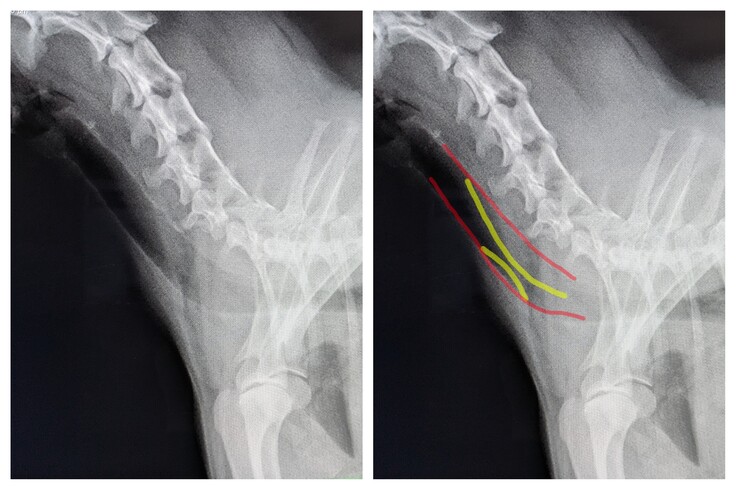

▲ポンタの気管です。通常赤い部分まであるはずの気管が黄色の部分まで潰れています。